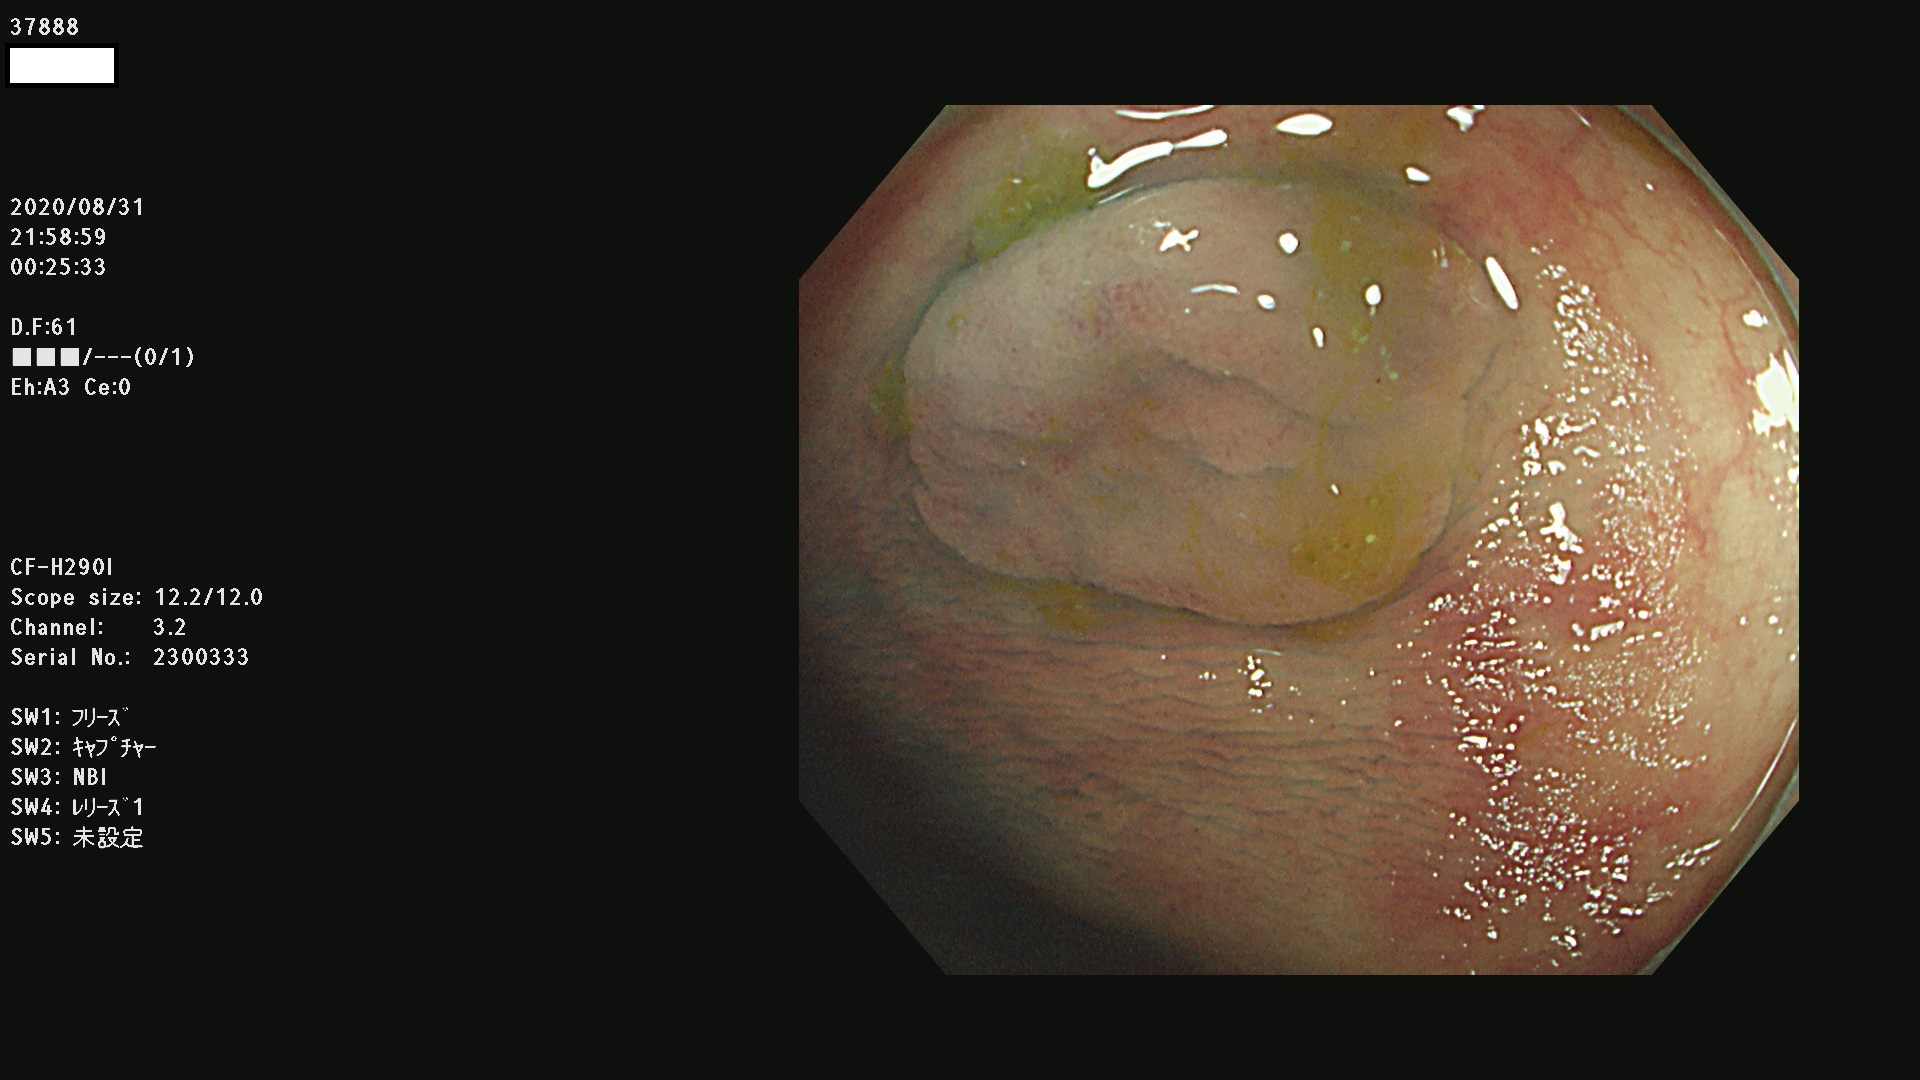

腺腫発見率 75 % (カルテ番号 37800〜37899の100名の方の検査結果で集計)大腸癌検診最新情報

以下のカルテ番号の方に腺腫(Adenoma,Group3〜5)が見つかりました(集計法)

37800(SSAPのみ) 37801 37802 37803 37804 37805 37806 37807 37808 37809(SSAPのみ) 37810 37811 37812 37813 37814 37815 37817 37818 37819 37820 37821 37822 37824 37825 37826 37827 37828 37829 37832 37833 37836 37837(SSAPのみ) 37839 37840 37842 37844 37845(SSAPのみ) 37847 37849 37850 37851 37852 37853(SSAPのみ) 37855 37856 37857 37860 37861 37862 37863 37864 37867 37868 37871 37874 37876 37877 37879 37880 37881 37882 37883 37886 37887 37888 37889 37890 37891 37892 37893 37894 37896 37897 37898 37899

発見困難で危険性の高い平坦型病変(上記100名より抽出) ![]()